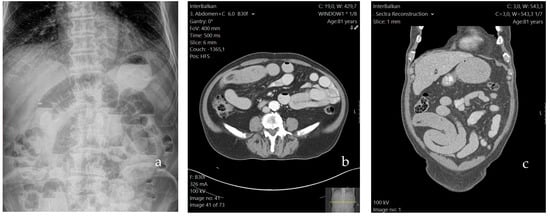

Initial imaging included chest and abdominal X-rays; the former was normal, while the latter revealed the presence of air-fluid levels in dilated loops of the small intestine, therefore confirming the initial diagnosis of an ileus (Figure 1a). The following day, an upper GI endoscopy (esophagogastroduodenoscopy) was performed, revealing mild gastritis of the intermediate region. The campylobacter-like organism (CLO) test was negative. On the same day, the patient underwent a contrast-enhanced abdominal computed tomography (CT) scan in order to decipher the cause of the intestinal obstruction. The results revealed proximally distended loops extending from Treitz’s ligament to the ileum, where a distinct transitional point was observed. In that particular segment, the ileum exhibited concentric thickening, indicating an intraluminal obstructive cause. Bowel loops distal to the obstruction appeared collapsed (Figure 1b,c). Additional findings included pericolic fluid retention, as well as fluid in the pouch of Douglas (POD), with slightly enlarged mesenteric lymph nodes adjacent to the caecum. Taking into consideration the patient’s advanced age, the above imaging findings raised suspicion of a possible malignancy.

Figure 1. The patient’s preoperative abdominal X-ray (a) and CT scan; axial (b) and coronal (c) plane.